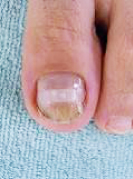

巻き爪、タコ、魚の目等があると症例に示すように、様々な症状を呈します。

早いうちに処置をして快適な生活を心がけましょう。